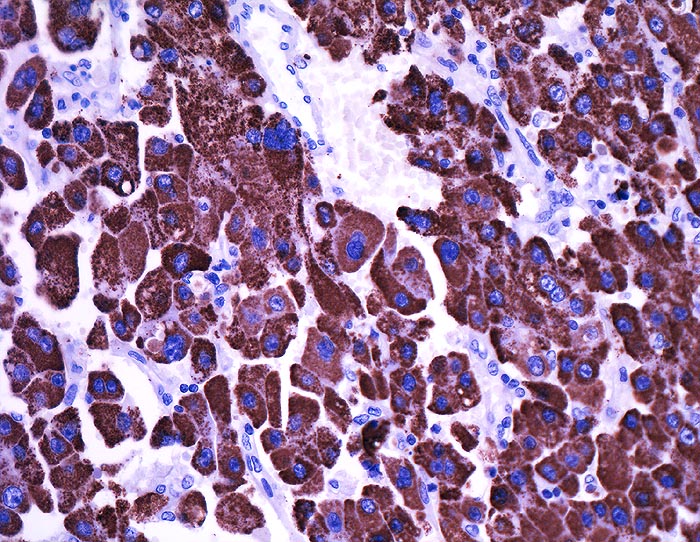

l/ HepPar1 (Hepatocyte)

HepPar1 (Hepatocyte)

Hep Par 1 (Hepatocyte Paraffin 1)

Anfärbung:

Zytoplasma grob granulär ohne canaliculäre Akzentuierung.

Reaktion im Normalgewebe:

Nicht neoplastische Hepatozyten sind diffus positiv. Regenerative Knoten zeigen eine heterogene Anfärbung. Normale Dünndarmschleimhaut kann fokal stark positiv sein. Alle anderen Normalgewebe sind negativ.

Reaktion in Neoplasien:

Hepatozelluläre Karzinome färben sich heterogener an als das Normalgewebe. Die Anfärbung korreliert nicht mit dem Differenzierungsgrad. Kombinierte hepatozelluläre und cholangiozelluläre Karzinome sind lediglich in der hepatozellulären Komponente positiv.

Gallenwegskarzinome, Pankreaskarzinome und Magenkarzinome sind selten positiv.

Diagnostischer Nutzen:

Unterscheidung des hepatozellulären Karzinoms vom cholangiozellulären Karzinom und von Lebermetastasen.